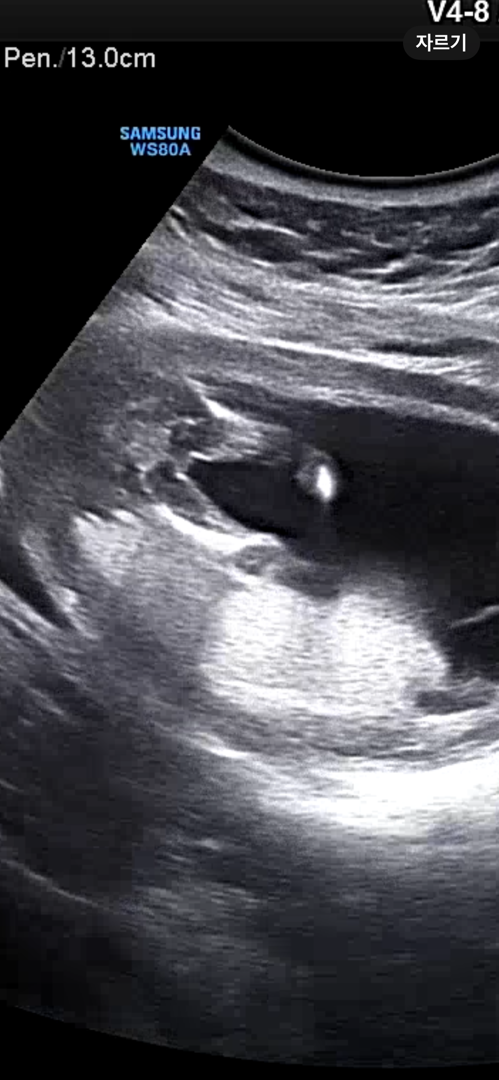

14주 딸 힌트..!!!확정?

이정도면 딸 확정일까요 ㅎㅎ 선생님은 처음에 오늘은 성별 못봐요~아직몰라요 하시더니 다 볼때쯤엔 그래도 전 내기하라하면 딸에걸래요~ 하시는게 독특한 힌트.....ㅎㅎ..14주에 가랑이 이정도면 딸 맞겟쥬~??

저 가랑이에 아주 살짝 볼록한게 소음순이 된다고 들었던거 같아요 ㅎㅎ